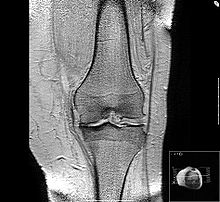

Mediale Gonarthrose MR-Darstellung eines arthrotischen Kniegelenkes. Deutlich zu sehen sind die Osteophyten im medialen (mittigen) und lateralen (seitlichen) Bereich des Gelenkspaltes und der Verschleiß oder Abrieb der Knorpelschicht im linken Bereich des Bildes. Der Knochen des Schienbeinkopfes im mittigen Bereich ist verdichtet, eine Reaktion auf den vermehrten mechanischen Stress. Die Knorpelschicht hat ihre Dämpfungsfunktion eingebüßt.